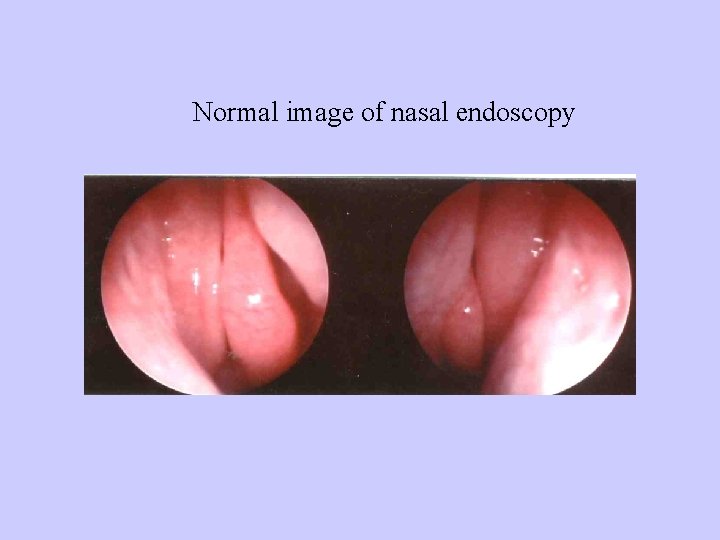

Normal image of nasal endoscopy